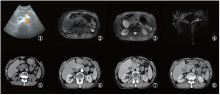

男性患者, 74岁, 因“ 发现胰腺肿物伴黄疸1月余” 入院。患者于2年前因上腹部疼痛在外院接受“ 胰腺炎” 治疗。出院后反复出现上腹部及剑突下疼痛, 行对症治疗效果不佳。1个月前再次出现上腹部疼痛, 在外院行对症治疗无好转, 症状逐渐加重遂来我院求诊, 我院门诊行上腹部CT检查提示胰腺肿物, 胆总管扩张。遂以“ 胰腺占位伴胆总管扩张” 收入外科, 拟行“ 胰腺肿瘤” 外科手术治疗。入院查血浆CA12-5、CA19-9、AFP、CEA值均正常。血浆D-二聚体升高(308 ng/mL), 血淀粉酶升高(283.5U/L), 黄疸指数(+)。彩超检查提示:胆囊肿大伴胆汁淤积, 肝内胆管及胰管扩张, 胰头区异常回声(占位性病变待排)(图1 ①)。MRI平扫显示:胰头区见结节状肿块, T1WI信号稍减低, T2WI信号稍减低(图1 ②~③); 磁共振胰胆管造影(magnetic resonance cholangio pancreatography, MRCP)提示胰头部肿块, 肿瘤性病变可能; 胰管、胆总管及肝内胆管扩张, 胆总管胰头部截断, 胆囊增大(图1 ④)。上腹部CT增强检查:胰头区见小片状稍低密度影, 边界不清, 动脉期病灶边缘强化, 静脉期及延迟期病灶逐渐呈充填式强化(图1 ⑤~⑧)。对上述各项影像学检查及生化指标进行综合分析, 初步诊断为胰头癌并梗阻性黄疸。故行经皮肝穿刺胆道引流术(percutaneous transhepatic cholangial drainage, PTCD)以缓解黄疸症状。鉴于目前缺乏病理学诊断依据, 对于胰腺癌的诊断尚缺乏最有力的证据, 决定行CT导向下胰腺穿刺活检术。活检细胞学HE染色显示:镜下见大量淋巴细胞及部分坏死细胞, 可见少量增大裸核(图2 ①~②)。病理检查提示:镜下见胰腺小叶间纤维组织增生伴大量慢性炎性细胞浸润, 以淋巴细胞、浆细胞为主, 小叶内少量慢性炎性细胞, 个别区域腺泡轻度增生, 未见其它特殊(图2 ③~④)。认为本例患者可疑诊断为IgG4-RAIP。

图1 治疗前彩超CT及MRI检查

注:①彩超检查显示:胰头区稍低回声区, 边界欠清, 病灶区未见明显血流信号; ②~④MRI平扫及MRCP检查:胰头区增大, T1WI信号稍减低, T2WI信号稍增高, MRCP显示肝内外胆管及胰管扩张; ⑤~⑧CT平扫及增强检查显示:胰头区增大, 见结节状等密度影, 边界不清, 胰管扩张; 增强扫描显示动脉期胰头区病灶轻度强化, 静脉期及延迟期表现为充填式强化

Fig.1 Preoperative ultrasonography, CT and MRI

Note: ① Ultrasonography showed that there was a slightly hypoechoic area in the pancreatic head area, the boundary was not clear, and no obvious blood flow was seen in the lesion area; ②~④ MRI scan and MRCP showed that the pancreatic head area was enlarged, the signal on T1WI was slightly decreased, and the signal on T2WI was slightly increased. MRCP showed that the intrahepatic bile ducts and pancreatic ducts were dilated; ⑤~⑧ Enhanced CT scan showed enlargement of pancreatic head area, nodular isodensity shadow, unclear boundary and pancreatic duct dilatation; enhanced CT scan showed mild enhancement of pancreatic head area in arterial phase, filling enhancement in venous phase and delayed phase